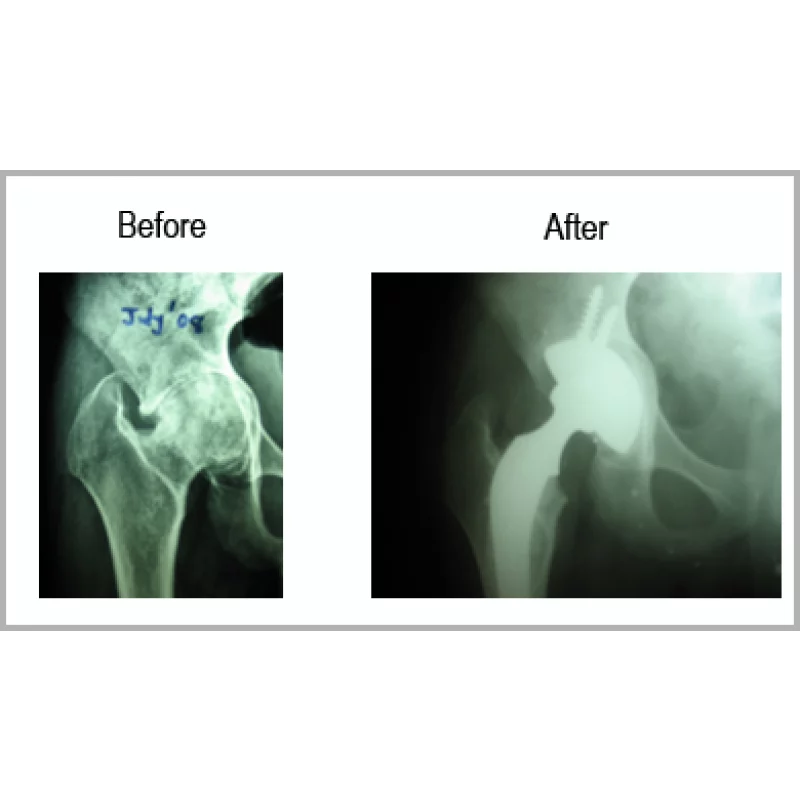

Protrusio Acetabulum

A Young Boy Aged 22 Years Had Fall From Height Before Few Years. He Had Injury Over Right Hip. He Did Not Have Proper Treatment. He Had Extreme Pain So Much So That He Could Not Keep His Right Foot On The Ground. He Had Shortening Of 2.5 Centimetres. He Had Protrusio Acetabulum.He Had Right Total Hip Replacement With Bone Grafting For Acetabulum. His Shortening Is Totally Corrected And Walking Normally.... Read more